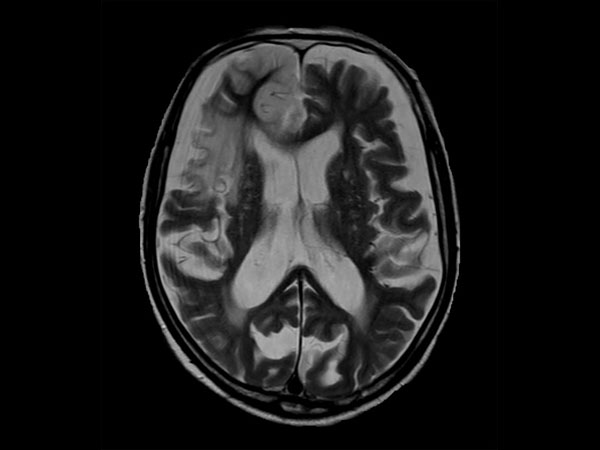

Acute stroke. Patient was brought to the first aid and directly transferred to the MRI unit. Axial studies were performed to get an overview of the stroke. Total study time is 9 minutes.

Axial T2w TSE